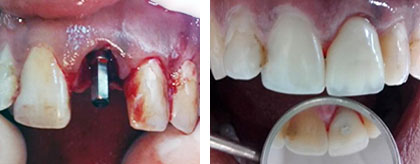

Se realizó radiografía inmediatamente después de concluida la fase quirúrgica y se procedió a la rehabilitación inmediata del caso. Por último nos cercioramos, dadas las condiciones del lecho implantario, de que la restauración provisional quedara completamente sin carga funcional, solo manteniendo el contorno y el perfil de emergencia ideal de los tejidos blandos (Fig. 2).

Fig 2 . Implante transalveolar y rehabilitación provisional inmediata.